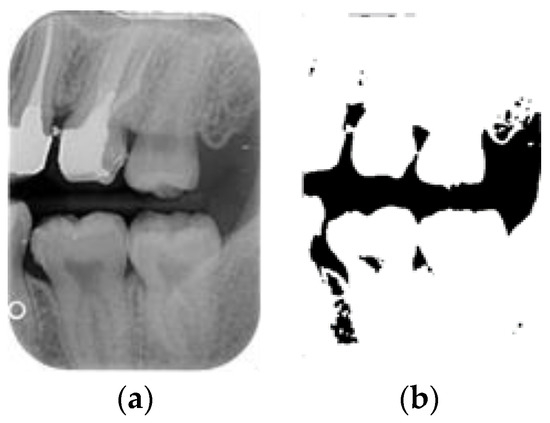

Dental calculus is recognized as a mineralized biofilm that comprises diverse calcium phosphate crystals, which may accumulate on the root surface both supra- and subgingivally [5]. A positive correlation between calculus deposits and periodontitis has been confirmed in multiple studies [6,7]. Despite clear evidence that the surface roughness of calculus alone does not initiate gingivitis, it is important to emphasize that calculus is consistently covered by an unmineralized layer of a viable biofilm [8], which is a primary factor in gingival inflammation [9]. The characteristics of dental calculus are not obvious in a BW image, as shown in Figure 1. The mechanical removal of subgingival plaque and calculus stands as the gold standard in the treatment of periodontitis [10]. While supragingival calculus can easily be seen and removed through sonic/ultrasonic instruments, subgingival calculus is invisible during intra-oral examination. Therefore, the identification of subgingival calculus is critical for the diagnostic process. Radiographic images have been widely used across various applications in the dental field [11]. Subgingival calculus is generally detected during periodontal probing, while radiographic examination can only show calculus on the proximal surfaces [12,13]. Meanwhile, Buchanan et al. [14] reported that the detection of dental calculus on the root surface by radiography had shown low sensitivity but high specificity, and a manual diagnosis can only detect dental calculus in 44% of the 275 datasets that truly have the condition. The detection ability can be increased to 82.2% by staining teeth with 1% methylene blue [15]. Galal et al. [16] observed that periapical films and intra-oral surveys showed comparable efficacy in calculus detection, with a particularly significant enhancement in detection when supplemented with radiographs. In comparison, other dental conditions like caries and periodontal disease have higher detection rates with manual methods. The detection rate for caries is approximately 70–85%, and for periodontal disease, it is around 65–80% [1]. Subgingival calculus documentation is crucial for periodontal assessment. Although clinical assessments are more common for detecting calculus, utilizing BW radiographs offers several advantages in calculus assessment. Firstly, BW images provide a comprehensive view of the tooth structure, allowing for a more thorough examination of interdental spaces where calculus often accumulates. Additionally, BW radiographs enable dentists to visualize areas that may be difficult to access during a clinical examination such as posterior regions. This enhanced visualization can aid in the early detection of calculus, leading to timely interventions and improved patient outcomes.

Figure 1.

Dental calculus symptoms on a BW image: (a) dental calculus symptoms; (b) absence of dental calculus symptoms.